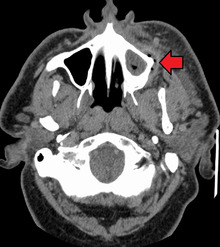

Dental caries can also cause bad breath and foul tastes.[16] In highly progressed cases, an infection can spread from the tooth to the surrounding soft tissues. Complications such as cavernous sinus thrombosis and Ludwig angina can be life-threatening.[17][18][19]

Complications | Inflammation around the tooth, tooth loss, infection or abscess formation[1][3] |